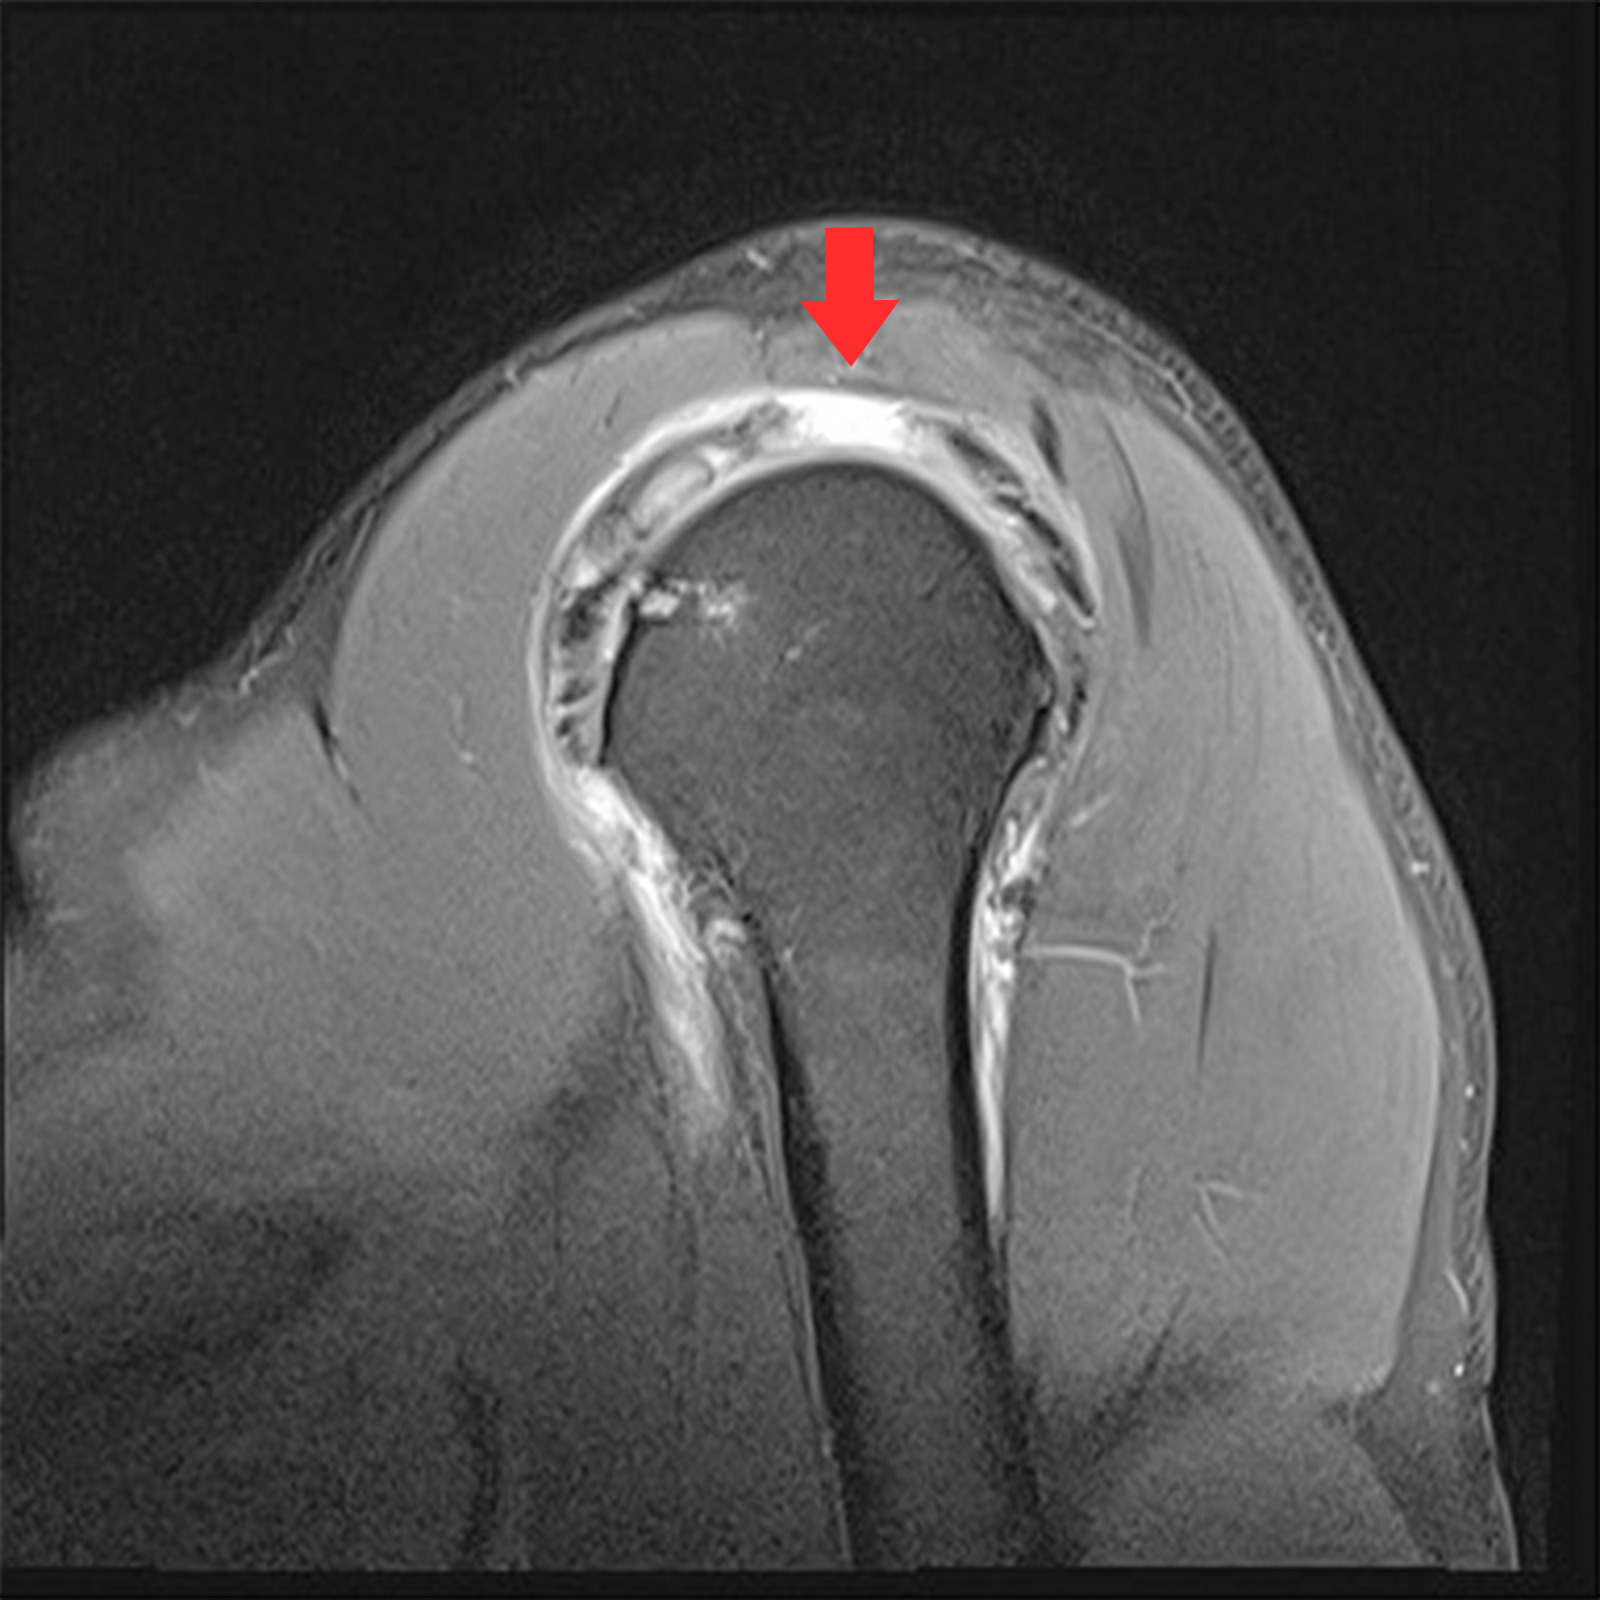

정상

회전근개파열

MRI 촬영시 정상적인 어깨의 경우 회전근개가 까맣게 나타나지만, 파열된 경우 하얗게 보여짐